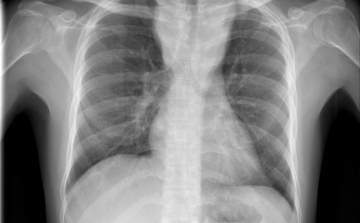

Egy líbiai menekülttáborból érkezhetett Európába a tbc egy új kórokozója

Menekültek révén, egy líbiai táborból érkezhetett Európába a tuberkulózis (tbc) kórokozójának egy korábban ismeretlen, gyógyszerekkel szemben ellenálló fajtája - írta a Die Welt című német lap a hírportálján szerdán.

Csökkent a tbc-fertőzések száma Európában

Átlagosan 4,3 százalékkal csökkent az új tuberkulózisos (tbc-s) esetek száma 2010 és 2014 között az Egészségügyi Világszervezet (WHO) 53 országot magába foglaló európai régiójában.

Van miért aggódnunk

A tuberkulózis, a kanyaró, a HIV és a rezisztens baktériumok terjedése aggodalomra adhat okot Európában – állapították meg a régió járványügyi szervezetének (ECDC) éves jelentésében.

40 millió dohányos halhat meg tbc-ben 2050-ig

A kutatók szerint akár a 40 milliót is elérheti azoknak a dohányosoknak a száma, akik 2050-ig tuberkulózisban (tbc) veszítik életüket.